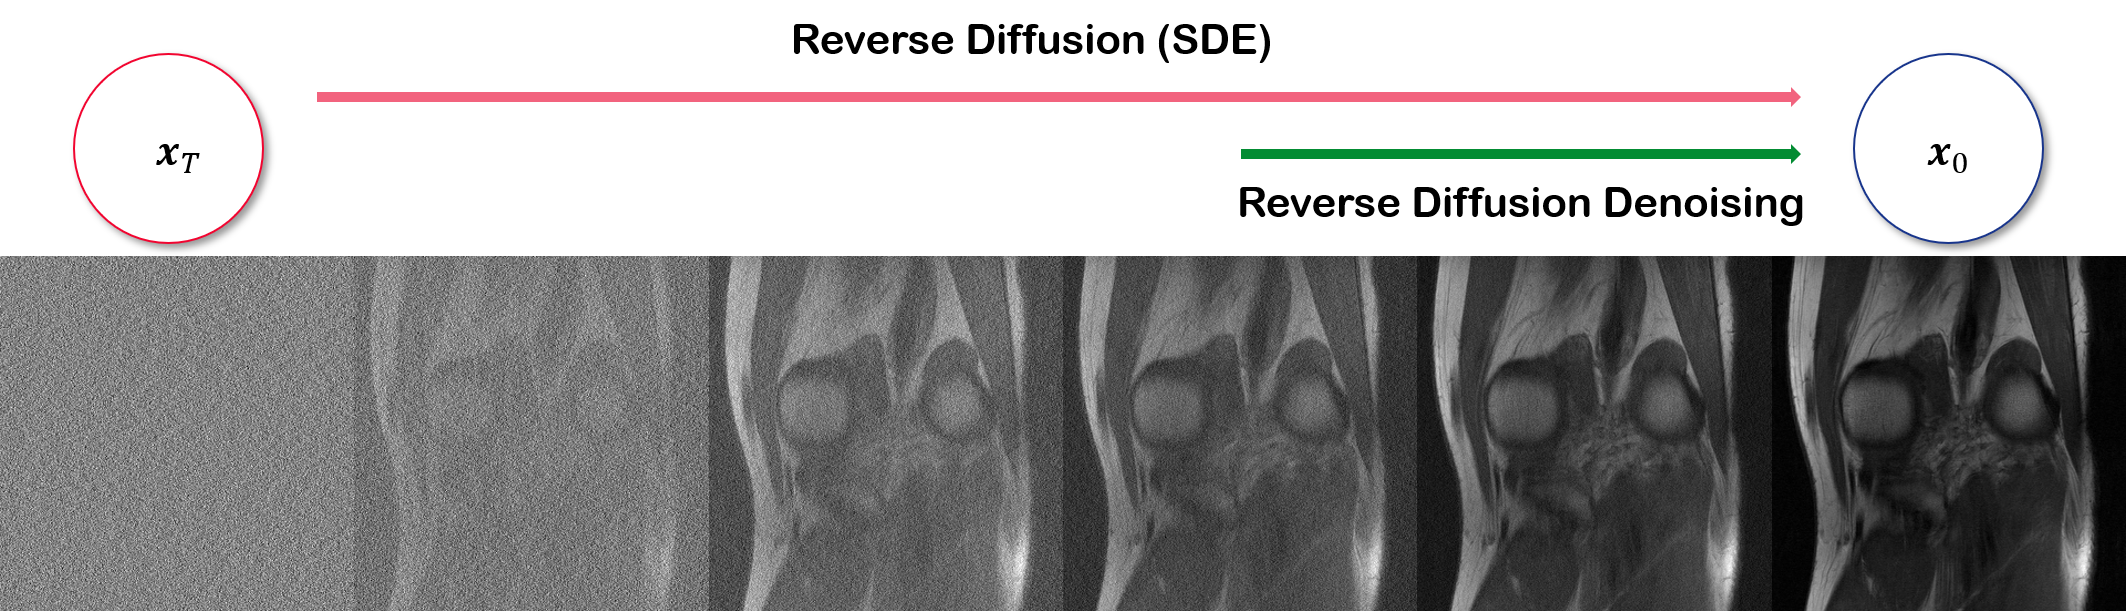

Refer to caption

Figure 5: Ablation study on low-frequency regularization method. (a) Without regularization, (b) with regularization, and (c) noisy image. First column: The alteration of the tortuous vascular structure might be misinterpreted as a round hepatic focal lesion by radiologists in clinical practice. Blue arrows indicate the region where structured shaggy artifact is present in the reconstruction without regularization. Second column: clearer vessel structure can be seen in the yellow arrows. White dotted lines indicate the results by the proposed method.

We study the effect of low-frequency regularization in Fig. 5. In the first column (see yellow arrow), we see that the vessel structure is altered when the regularization is not performed. Contrarily, the structure is conserved with the regularization present. Furthermore, in the blue arrow of the first column of Fig. 5, we observe some shaggy-looking structured artifact when we do not perform any regularization. Again, this artifact is eliminated as we impose our regularization. Consistent with the observation that was made in the first column, we again see altered structure in the second column, when regularization is not imposed. Thus, we can safely conclude that the proposed regularization is able to lead our reconstructions toward a conservative outcome, thereby eliminating false positives/negatives.